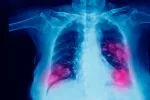

Un estudio del Centro de Investigación Médica Aplicada (CIMA) y de la Clínica Universidad de Navarra ha demostrado en ratones que cuando se bloquea una proteína antes de iniciar el tratamiento de inmunoterapia contra el cáncer de pulmón, de riñón o el melanoma se mejora la eficacia de la misma y se reduce su toxicidad. La investigación se ha publicado en la revista Nature.

La inmunoterapia aplicada contra el cáncer busca que el sistema inmunitario del enfermo destruya las células cancerosas. El PD-a y CTLA-4 son proteínas que se encuentran en los Linfocitos T y evitan que estas destruyan otras células, entre ellas, las cancerígenas. Cuando se inhiben, se estimula la acción inmunitaria del organismo. El problema es que los medicamentos que emplean para bloquearlas provocan en el 40% de los pacientes importantes efectos secundarios. Tanto que, aunque el tratamiento con anti-PD-a y anti-CTLA-4 es muy eficaz en enfermos con cáncer de piel o renal con metástasis, en un tercio de los casos debe interrumpirse por secuelas adversas autoinmunes.